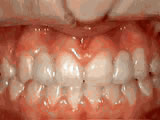

Open bite – Front teeth don’t touch

Patient sucked her thumb as a young child. She started treatment at age 13. She had braces and a special appliance — called a crib — to retrain the tongue, for 28 months. Now she can bite the lettuce out of a sandwich.